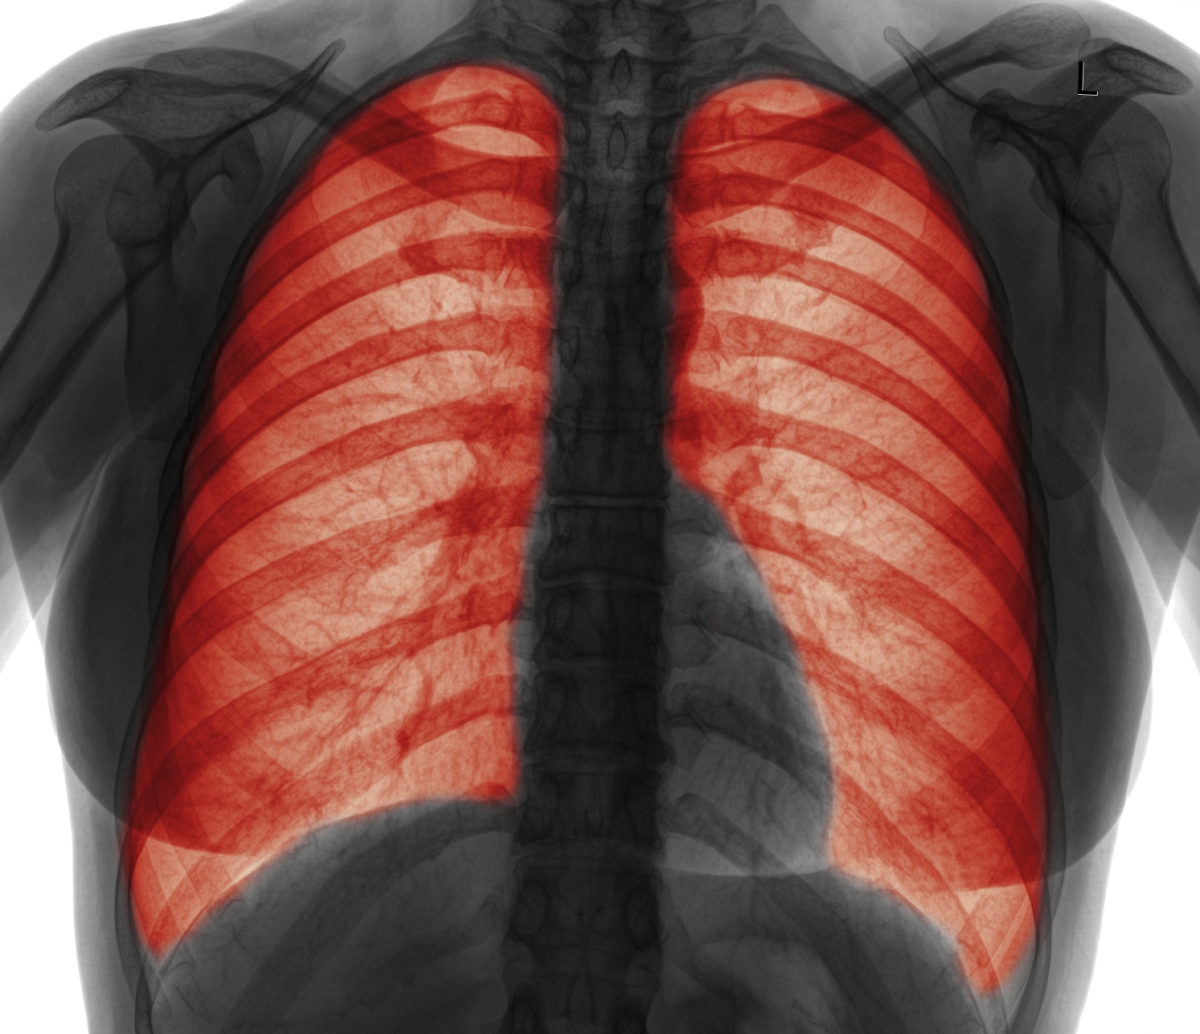

Lung diseases such as CF are difficult to treat because of the accumulation of mucus that clog the airways. This means drugs cannot be delivered to the affected tissues effectively.